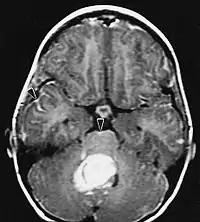

Sur-L'IRM montre une tumeur intracrânienne comme une lésion massive qui peut devenir plus luminescente après utilisation du produit de contraste. Cependant, il y a toujours une anomalie de signal dans -L'imagerie par résonance magnétique, qui indique la présence d'une néoplasie ou d'un œdème vasogénique. Habituellement, une luminescence accrue (amélioration du contraste) indique une tumeur d'un grade supérieur de malignité. Un anneau de contraste est caractéristique du glioblastome, avec la partie luminescente correspondant à la partie vitale de la tumeur maligne, et la plus foncée - zone hypointense correspondant à une nécrose tissulaire.

L'IRM montre généralement une lésion de contraste massive impliquant le cervelet. Comme mentionné ci-dessus, le médulloblastome a une forte propension à infiltrer localement les leptoméninges ainsi qu'à se propager à travers l'espace sous-arachnoïdien, impliquant les ventricules, la convexité cérébrale et les surfaces leptoméningées de la colonne vertébrale. Par conséquent, il est nécessaire de mettre en résonance tout l'axe crânio-spinal.

Les patients souffrent d'une variété de symptômes caractéristiques d'une lésion massive focale ou multifocale. L'IRM montre généralement des tumeurs avec un rehaussement de contraste homogène au sein de la substance blanche périventriculaire profonde. La multifocalité et le rehaussement inhomogène sont typiques des patients dont le système immunitaire est affaibli. L'analyse du lymphome du SNC est extrêmement importante dans le diagnostic différentiel de la néoplasie cérébrale. Il est à noter que l'administration de corticoïdes peut entraîner la disparition complète du rehaussement, rendant difficile le diagnostic des lésions. Par conséquent, si un lymphome du SNC doit être pris en compte dans le diagnostic différentiel, les corticoïdes doivent être évités à moins que l'effet de masse ne provoque un problème grave et immédiat chez le patient.